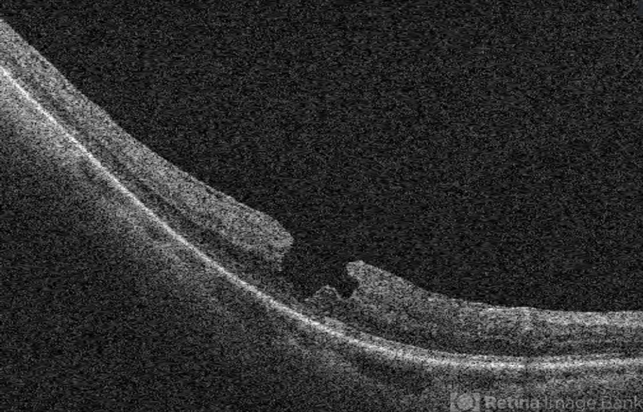

- Lamellar Macular Hole

- Lamellar macular hole.